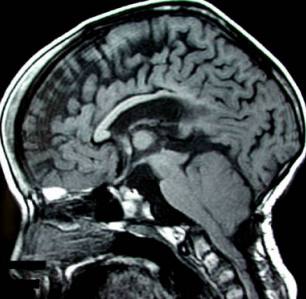

图1a 轴位 T2 加权磁共振成像显示侧脑室呈“巨脑室”表现,后部扩张,前角呈裂隙状。b 矢状位 T1 加权成像示后颅窝狭小拥挤,伴 Chiari II 型畸形及小脑幕部分发育不全。c 磁共振血管成像序列显示静脉窦的多发异常,尤其为上矢状窦狭窄、直窦垂直走行以及横窦位置极低。d、e、f 冠状位层面从前向后依次展示脑室解剖(每幅图右上角给出矢状参考平面):第三脑室前部狭窄,中部几乎完全被巨大中间块占据,后部呈显著囊性扩张。

图2 矢状位 T1 加权脑像显示脑脊液循环的主要阻塞部位:导水管狭窄及第四脑室脑室层面的消失;桥前池囊性扩张;后颅窝结构拥挤;蛛网膜下腔层面枕骨大孔阻塞。